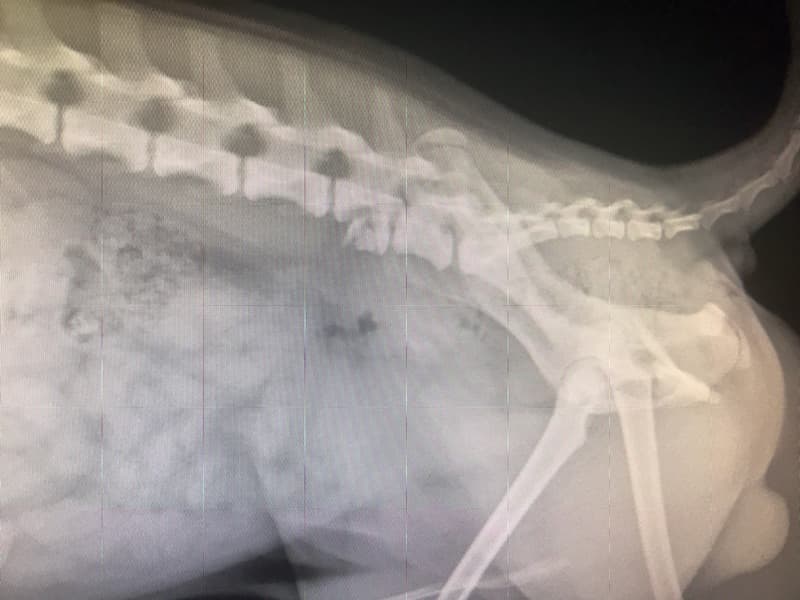

05/03/18- When I was at work, Maple got out of the house and ran out into the street (Bolsa and Bushard) and was hit by an oncoming vehicle. Fortunately Maple survived but was left with a broken leg and damaged spine. The vet said that it would cost 3k for the leg surgery and 7k for the spine surgery and I don't have the money to pay for his medical expenses. I know that people are always fundraising for other causes but if you can even spare a dollar, I would really appreciate it. He's the reason I wake up everyday with a smile. He's the happiest dog in the world and seeing him so sad breaks my heart =((